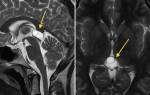

- Компьютерная томография позволяет понять точное местонахождение и размеры повреждений, особенно если речь идет о средостении.

После комплексной диагностики врач определяет причины, которые повлекли увеличение узлов средостения. Лабораторные и инструментальные способы определят движущие силы нарушения. Данная патология исследуется способом компьютерной томографии (КТ), УЗИ (ультразвуковое исследование) грудной клетки, проведением МРТ (магнитно-резонансной томографии).

Больного с положительным результатом на иммунологический тест отправляют на КТ обязательно. Грудная клетка подвергается линейной томографии в исключительных случаях, когда нет альтернативы. Делают флюорографию, рентгеноскопию, выводят на табло прибора трёхмерный снимок.

Сегодня для диагностики средостенной лимфаденопатии применяют компьютерную визуализацию. При этой процедуре специалисты получают самую достоверную информацию. С помощью бронхоскопии медики получают материал для исследования трахеи, бронхов, туберкулёза. Радиография исследует кровообращение и вентиляцию лёгких.